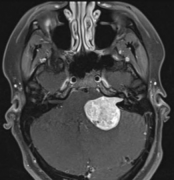

脑膜瘤

脑膜瘤严重吗?脑膜瘤事实解读

脑膜瘤是脑膜上的肿瘤。头骨保护大脑。在头骨内部,覆盖大脑...